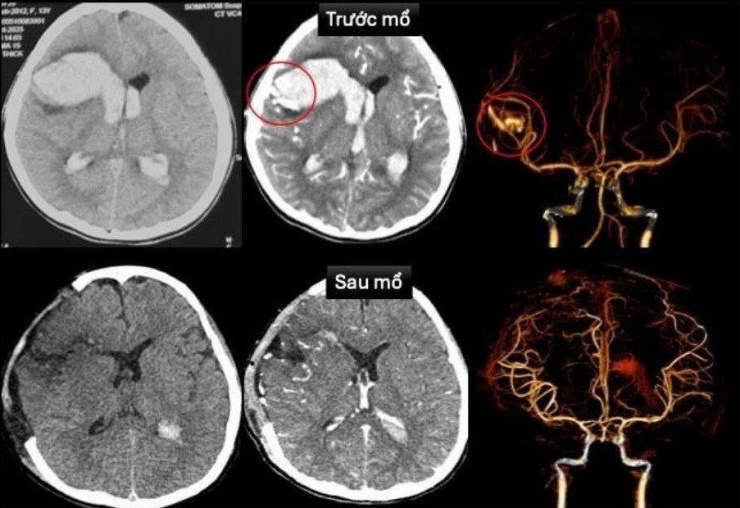

Tại đây, kết quả chụp cắt lớp vi tính sọ não dựng hình mạch máu cho thấy bé bị vỡ dị dạng động – tĩnh mạch vùng trán bên phải gây xuất huyết lan vào nhu mô não và não thất. Qua siêu âm tim, bác sĩ đồng thời phát hiện trẻ mắc bệnh cơ tim xốp. Đây là tình trạng thành cơ tim có cấu trúc xơ rỗng, dễ gây rối loạn nhịp và suy tim.

Vùng xuất huyết do vỡ dị dạng mạch máu não ở bệnh nhi trước và sau phẫu thuật

Hiện tại, bệnh nhi đã tỉnh táo, có thể trò chuyện, chỉ còn yếu nhẹ chân phải. Hình ảnh chụp não sau mổ không còn dị dạng mạch máu, chức năng tim hồi phục tốt. Bé đã được rút máy tạo nhịp, ngưng thuốc vận mạch và chuẩn bị xuất viện.